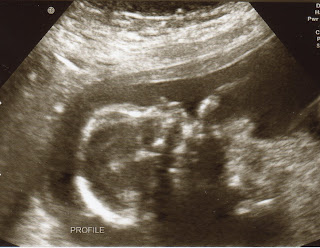

Average weight at the halfway point is 9-15 ounces and Jack is on the lowest end at 9 ounces. He is such a cutie though! According to the ultrasound nurse, everything looked absolutely great and we could not be more thrilled! She took so, so, so, sooooooooooo many pics for us! She was the sweetest tech (hadn't had her yet) and was very personable and engaged in being thorough with all her checks of our guy. I even told her I was hoping to get some good pics to add to our Christmas card and she went crazy with the picture taking...it was AWESOME!!!Jack was a mischievous little bunny today! Whenever she wanted to get a certain angle, she'd have to have me move all different ways because he'd kinda throw his hand up and then roll the opposite way...made things kinda tough, the ornery little thing...tee-hee! I guess a rowdy boy is what his daddy and I both deserve after the hell we gave each of our parents when we were little!

Here are some of the TONS of pics we got today! Enjoy!

| He's just chillin' here with his leg up and I LOVE it! |